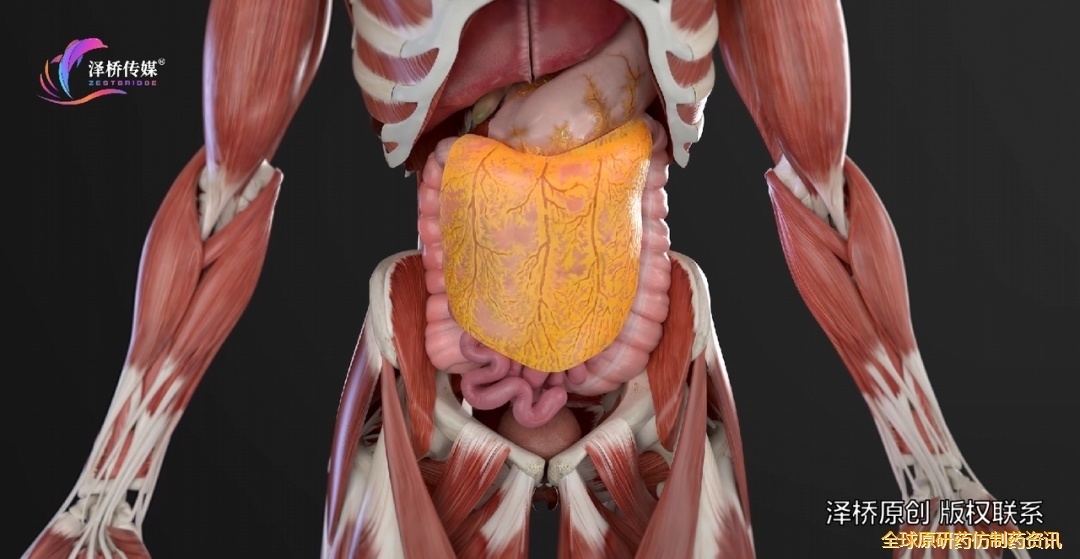

腹膜后腔包含多个重要器官,如肾脏、胰腺,以及下腔静脉和腹主动脉等(图1)。这些结构彼此紧密相邻,因此容易受到腹膜后肿瘤的压迫。因此,术前需要进行影像。

图1 腹膜后间隙的解剖